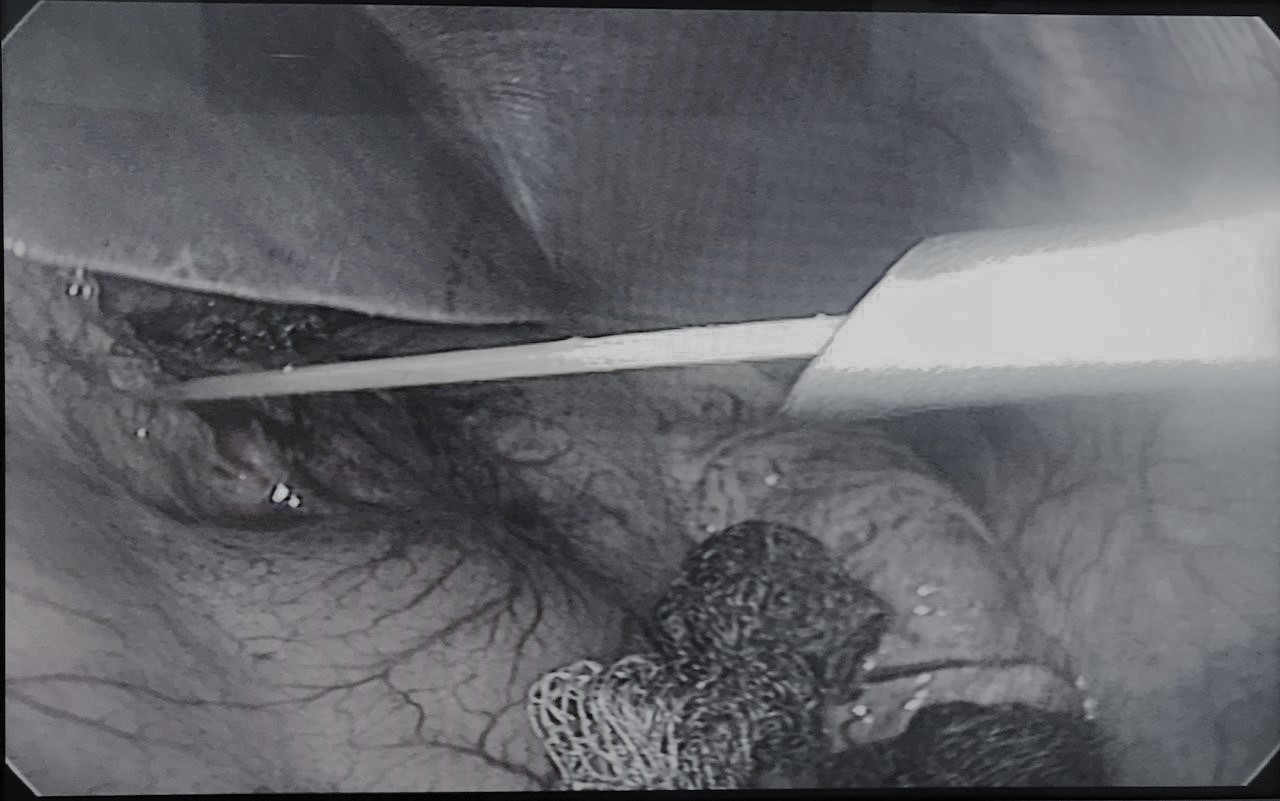

Một số hình ảnh ghi nhận trong và sau mổ:

Hình 5: Cây tăm tre được rút ra khỏi gan trái

Hình 6: Cây tăm tre được lấy ra ngoài qua lỗ troca 5mm.

Hình 7: Cây tăm tre được lấy ra ngoài với chiều dài gần 7cm

Bệnh nhân được hội chẩn và được chỉ định nhập viện Khoa Ngoại Tiêu Hóa để được tiếp tục theo dõi và điều trị. Sau 3 ngày điều trị, tình trạng đau bụng bệnh nhân tăng nhiều hơn, thăm khám ấn vào vùng thượng vị cho thấy tình trạng đau tăng hơn nhiều, kèm cảm ứng phúc mạc (+) nên bệnh nhân đã được chỉ định mổ cấp cứu bằng phẫu thuật nội soi vào tối cùng ngày. Kết quả phẫu thuật cho thấy mặt dưới gan trái tạo thành khối viêm dính kích thước 30x20mm, phẫu thuật viên đã tiến hành phẫu tích và lấy ra 1 chiếc tăm tre dài 70mm xuyên thủng vào trong gan trái, kiểm tra dạ dày không phát hiện lổ thủng, các tạng khác không thấy tổn thương. Sau phẫu thuật 2 ngày, bệnh nhân ổn định, bụng mềm, vết mổ khô, ăn uống được, trung đại tiện bình thường. Dự kiến sẽ cho ra viện trong vài ngày tới.